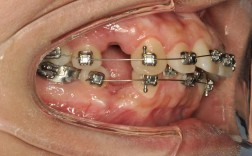

正畸牙钉,在临床上常被称为“微种植体支抗钉”,是正畸治疗中用于施加精准、稳定支抗的重要辅助工具,它的主要作用是在牙槽骨中提供“支点”,帮助医生在移动目标牙齿时避免其他牙齿发生不必要移位,尤其对于复杂病例(如深覆颌、牙齿严重拥挤、前突等)的治疗效果提升至关重要,而正畸牙钉的材质选择直接关系到其生物相容性、机械稳定性、耐腐蚀性以及患者的治疗体验,目前临床上常用的材质主要有钛合金、医用不锈钢、生物陶瓷等几类,每种材质均有其独特的特性与适用场景。

钛铝合金则通过添加铝和钒元素,进一步提升了材料的强度和韧性,使其在承受正畸施力时不易变形或断裂,钛合金的弹性模量(约100-110 GPa)与人体骨组织(约10-20 GPa)接近,能有效减少“应力遮挡效应”(即植入物因过刚而导致骨组织受力减少、萎缩),保障牙槽骨的长期稳定性,临床中,钛合金牙钉通常会进行表面处理(如喷砂酸蚀SLA、阳极氧化等),以增加表面粗糙度,促进骨细胞附着,缩短骨结合时间(通常为2-3个月)。